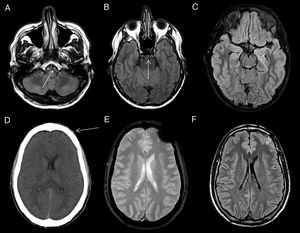

Figure 7.Leptomeningeal carcinomatosis. Patient with a history of lung cancer with signs of leptomeningeal dissemination with signal hyperintensity in bilateral frontoparietal convexity sulci on FLAIR imaging (A), which show enhancement with intravenous contrast in both the FLAIR sequence with contrast (B) and in gadolinium-enhanced T1 with magnetisation transfer (arrow in C). Secondary leptomeningeal melanosis. Patient with metastatic melanoma with signs of bilateral leptomeningeal infiltration on SPIR FLAIR images (arrows in D) and with areas of leptomeningeal uptake on FLAIR (E) and gadolinium-enhanced T1-weighted sequences with magnetisation transfer (F).

Secondary leptomeningeal lymphomatosis by contiguity. The FLAIR image (A) shows hyperintensity in the sulci between the cerebellar folia (arrow) due to leptomeningeal infiltration contiguous to a cerebellar lymphomatous mass showing intense enhancement on the gadolinium-enhanced T1-weighted sequence (B) and diffusion restriction (C). Leptomeningeal involvement shows uptake in the T1-weighted sequence after Gd administration (D).